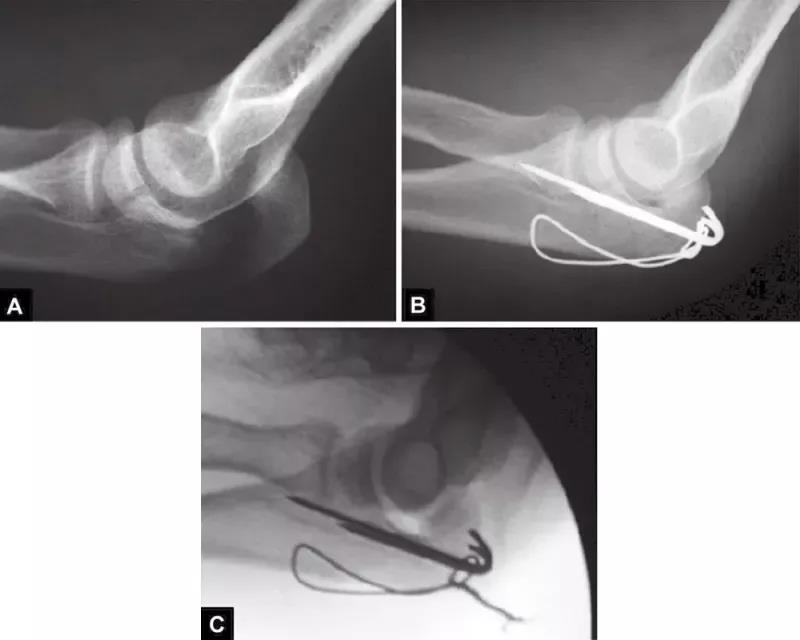

当存在鹰嘴关节面部分压缩时,必须将其对应肱骨滑车抬高复位。在三头肌止点用钢丝牵开鹰嘴尖端(图4),复位压缩骨折,用细克氏针将其推靠在肱骨滑车上维持位置。克氏针必须紧贴压缩骨折部位的软骨下骨来维持位置。此时,用高质量的侧位X线片检查来确定压缩骨折的复位,克氏针的位置是否良好是非常必要的。另一种方法是采用松质骨植骨来支撑复位的压缩骨折。

图4A和B(1)将鹰嘴拉下复位关节内松动的骨片,用横向箭头所示细克氏针,将其推挤在滑车上维持复位;(2)钢丝环穿过三头肌止点周围将鹰嘴拉下;(3)克氏针紧贴软骨下骨插入支撑松动的关节内骨片(给向箭头所示克氏针)